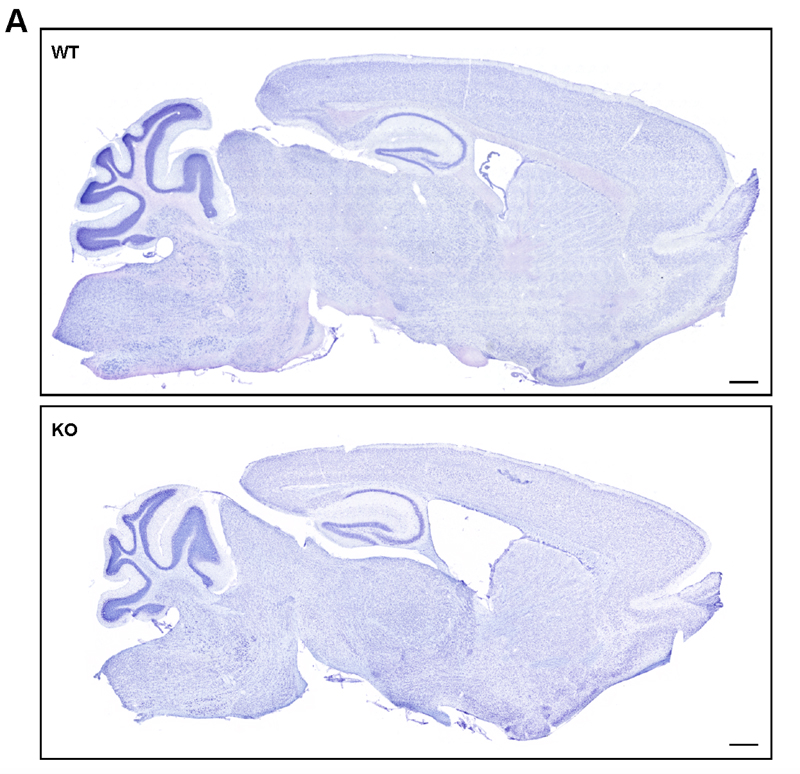

Caption Neuroanatomical abnormalities in the Ube3btm1a(EUCOMM)Hmgu/Ube3btm1a(EUCOMM)Hmgu (KO) mice. Nissl staining of brains from mutant (KO) and wild-type (WT) mice revealed a hypoplastic corpus callosum, enlarged ventricles, and decreased thickness of the primary somatosensory cortex in the KO compared to WT. The thickness of the primary motor cortex was not different. Representative images of Nissl stained brains (A). (corpus callosum area: *P=0.0153, ventricle area: *P=0.0196, thickness of the somatosensory cortex: *P=0.0376, n=3 WT, 3 KO). Scale bars, 500 um.

Copyright This image is from Cheon S, Proc Natl Acad Sci U S A 2019 Feb 26;116(9):3662-3667. Copyright 2019 National Academy of Sciences, U.S.A. J:273879